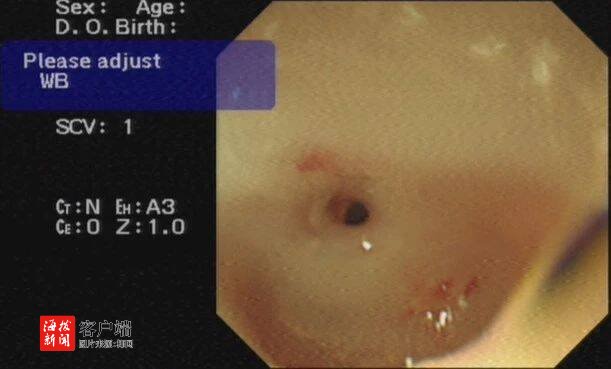

然而,首次胃镜检查就让治疗陷入僵局:食管距离门齿约24cm处显著狭窄,导丝及球囊扩张导管难以通过,常规的内镜扩张治疗面临巨大挑战。面对狭窄段长达10cm的重度食管狭窄,单纯内镜治疗难度极大。

4月16日,由消化内科蔡笃雄主任医师、高飞主治医师,介入血管外科孙刚副主任医师、廖勇主治医师,介入导管室林子义技师、谢春花副主任护师等组成的精锐手术团队严阵以待。内镜下,食管狭窄处仅露出一条细小缝隙,手术难度极高。但在X射线透视的精准引导下,手术团队凭借丰富经验和高超技艺,经过多次尝试,终于让导丝成功穿过狭窄段进入胃腔!随后,5mm和8mm扩张球囊逐级撑开狭窄食管,最后顺利置入食道金属支架。造影剂顺利通过食管狭窄段进入胃腔,此次高难度手术取得良好效果。